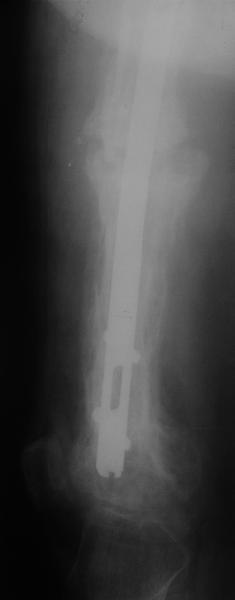

Пациент 82 лет, поступил через 5 мес. с несросшимся переломом после открытого интрамедуллярного остеосинтеза. Выполнили реостеосинтез стержнем 12 мм. ( мах. доступного нам в 2003 г.) Через 4 мес динамизация. В течении 2х лет сращения нет, тем не менее конечность опорна (ходит с тростью). От очередного реостеосинтеза отказались из-за сопутств. патологии.

Еще один пример. Пациентка с юга России, прислала рентгенограммы через год. На сегодня прошло 2 г. 8 мес. после операции. Несмотря на не очень убедительный процесс сращения, пациентка ходит. Учитывая остеопороз при Педжете, решили, что динамизировать вообще не нужно.